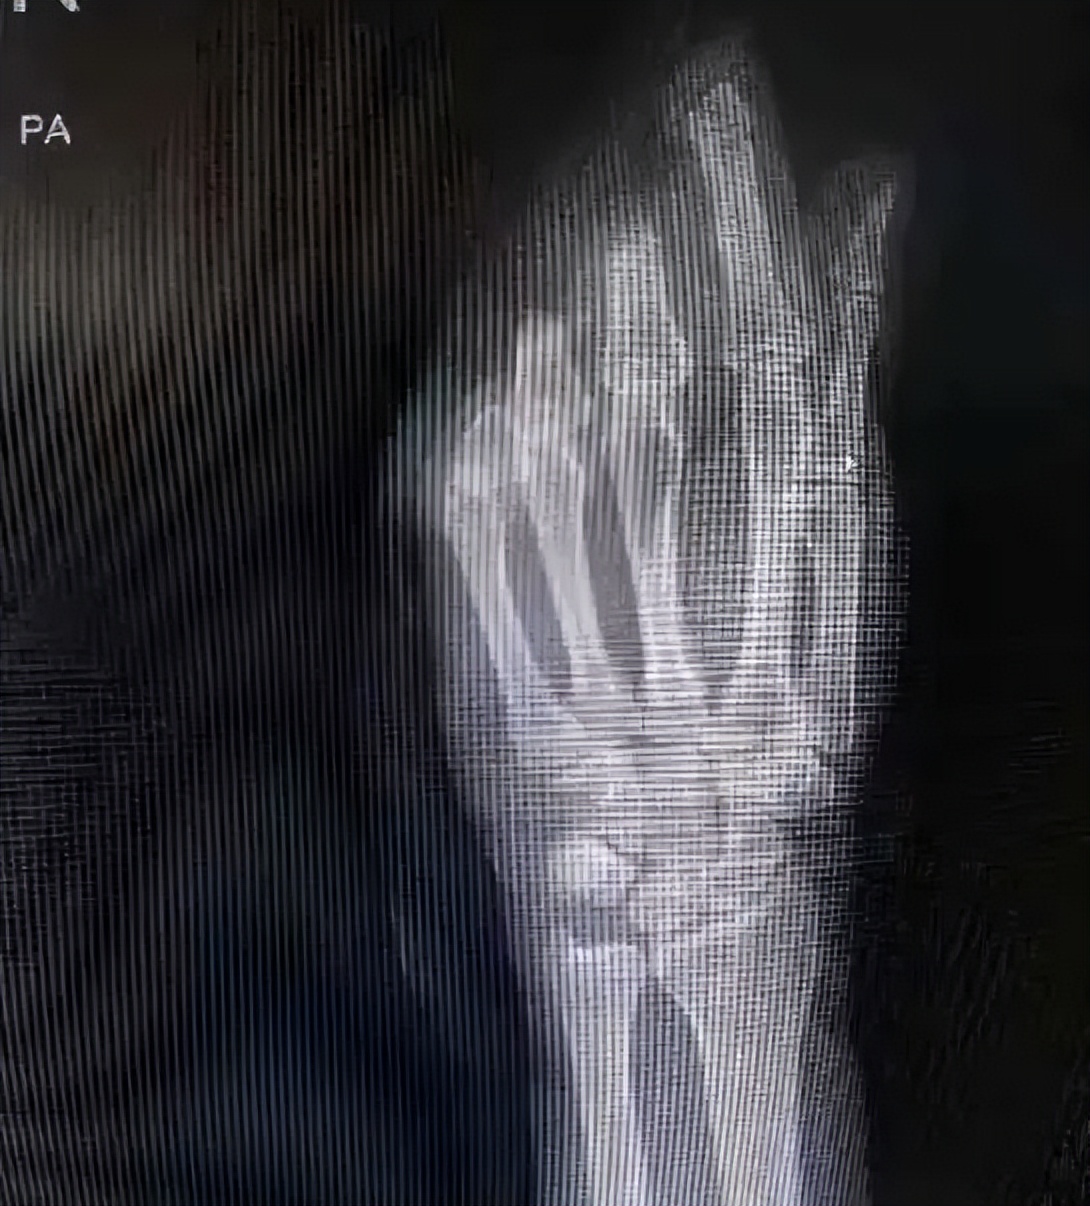

CT显示手指断离情况

钱姨四根手指完全断离